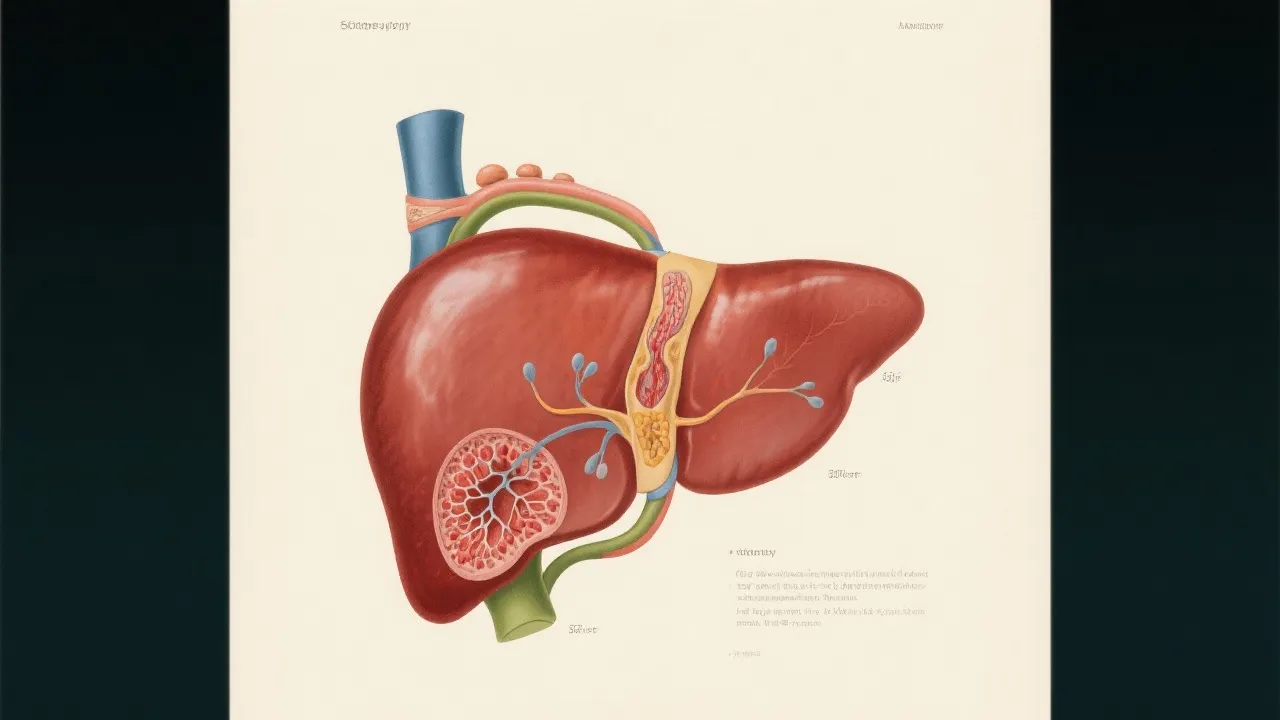

Cyp2e1 and Its Impact on NAFLD

Cyp2e1's Impact on NAFLD

Understanding Cyp2e1’s Role in NAFLD

The Role of Cyp2e1 in NAFLD

Cyp2e1's Role in NAFLD Understanding

Understanding Cyp2e1's Role in NAFLD

Understanding Cyp2e1 in NAFLD

Cyp2e1 and Nafld: A Molecular Connection

Cyp2e1 NAFLD: A Multifactorial Perspective

Cyp2e1 Role in Nafld

Understanding Cyp2e1's Role in NAFLD

Cyp2e1's Role in NAFLD